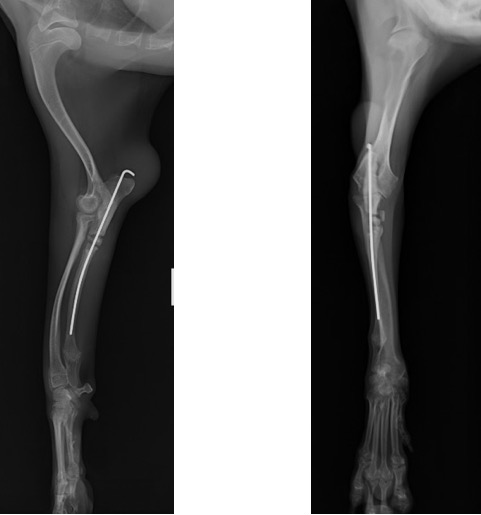

術前計画としてCT検査を実施し、肘関節の整合性を確認した後に、橈骨の湾曲防止と肘関節の不整合を矯正するために尺骨の骨切術を実施しました。

術後のLateral像とAP像 (骨切り後に尺骨のアラインメントを合わせるために髄内ピンとして1.2mm K-wireを刺入しました)